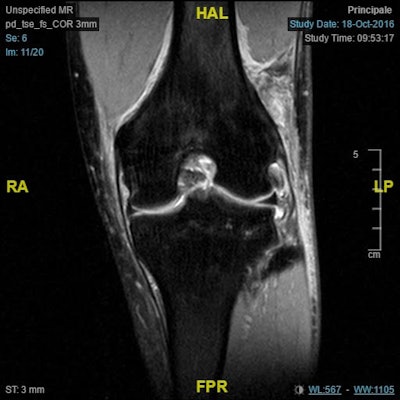

A team of Italian researchers found that MRI was highly accurate for finding abnormalities of the anterolateral ligament (ALL) and capsule, correlating significantly with surgical results. On the downside, the modality wasn't quite as proficient at identifying abnormalities in the iliotibial (IT) band or determining whether ALL/capsular tears were partial or complete, according to the researchers led by Dr. Edoardo Monaco from the Sapienza University of Rome in Italy.

"The most important finding of this study was that when surgical exploration was the gold standard, MRI evaluation demonstrated high sensitivity, specificity, and accuracy for detection of abnormalities of the ALL/capsule," the authors wrote. "The sensitivity and specificity for other parameters were not as high, such as whether there was a complete tear or not and anterior/posterior extension; for evaluation of the IT band, the values were low."

Abnormalities in the ALL and capsule were found on MRI in 22 (88%) of the 25 cases that were confirmed from surgery as abnormal. However, MRI was less effective for other diagnoses, such as detecting abnormalities in the IT band and determining whether ALL/capsule tears were partial or complete, and if the extension of the capsular tear was posterior or anterior.